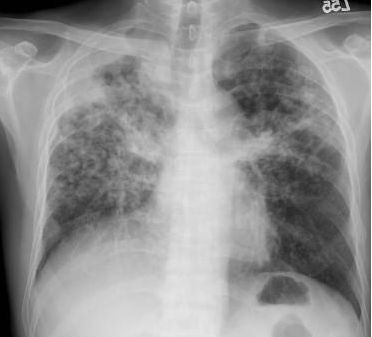

6. 一位42歲男性陳述咳嗽二個月之久,胸部X光如圖所示,請問下一步優先採取的檢查為何?

(A) 痰抹片查抗酸菌及培養分枝桿菌 (B) 痰抹片做革蘭氏染色及培養一般細菌 (C) 查血清人類免疫不全病毒(HIV) (D) 做胸部高解析度電腦斷層(HRCT) (E) 做支氣管鏡檢查,必要時做切片檢查